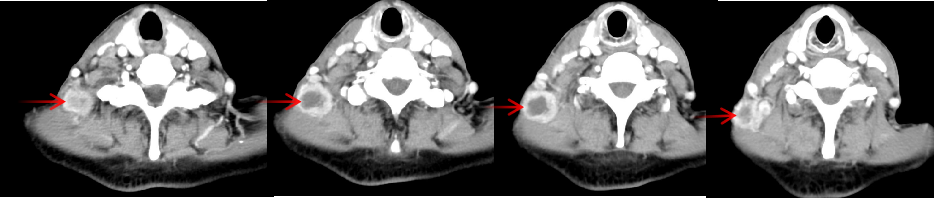

林老先生,67歲,患者2024年8月因咳嗽、咳痰,并發(fā)現(xiàn)頸部包塊入院。入院后經(jīng)CT檢查發(fā)現(xiàn),肺內(nèi)及頸部可見多發(fā)腫瘤病灶(見圖)。于2024年8月21日行超聲引導(dǎo)下頸部淋巴結(jié)穿刺活檢術(shù)。術(shù)后病理提示:右頸轉(zhuǎn)移性肺腺癌。頭部磁共振檢查顯示,顱內(nèi)多發(fā)腦轉(zhuǎn)移瘤病灶(見圖)。診斷為肺腺癌,腦、頸部淋巴結(jié)、肺內(nèi)多發(fā)轉(zhuǎn)移IVB期。進(jìn)一步對(duì)患者腫瘤組織進(jìn)行腫瘤組織基因檢測(cè)和免疫檢查點(diǎn)分子——細(xì)胞程序性死亡配體1(PDL1)檢測(cè)。

圖注:CT檢查,肺內(nèi)及頸部可見多發(fā)腫瘤病灶。

患者基因檢測(cè)結(jié)果為陰性,沒有找到具有靶向治療藥物的突變基因。此外,患者年齡較大,體質(zhì)非常瘦弱,全身多發(fā)轉(zhuǎn)移病灶,為治療帶來了巨大的挑戰(zhàn)。然而,患者PDL1檢測(cè)顯示,PDL1高表達(dá)(PD-L1患者TPS98% CPS100%),提示免疫治療有效率較高。潘振宇教授團(tuán)隊(duì)為患者制定了個(gè)體化精準(zhǔn)腫瘤治療方案,患者于2024年9月21日開始接受頭部放療。采用最新一代智慧化精準(zhǔn)放療系統(tǒng)——Halcyon“速銳刀”,成功控制患者全部顱內(nèi)病灶。治療過程順利,沒有副反應(yīng)發(fā)生。隨后,給予患者每3周1次免疫治療。經(jīng)過3次免疫治療后復(fù)查,患者肺內(nèi)病灶顯著縮退,癥狀明顯恢復(fù),沒有明顯副反應(yīng)發(fā)生。目前狀態(tài)恢復(fù)良好,生活完全自理。

圖注:治療后復(fù)查胸部CT顯示,肺內(nèi)病灶明顯縮小,頸部淋巴結(jié)轉(zhuǎn)移病灶基本消失。